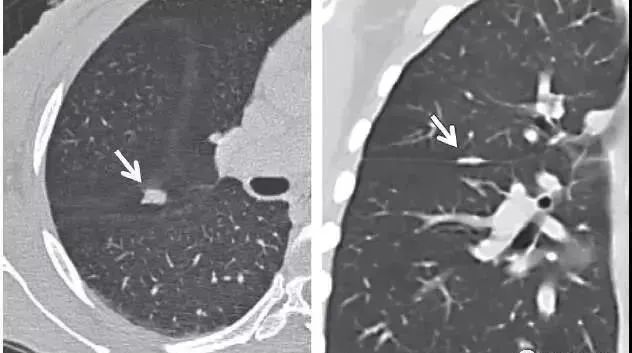

横看成岭侧成峰,下图CT扫描时显示的是叶间裂上的一个结节影(图1),而CT冠状面重建则显示该结节影其实为线状的疤痕或淋巴组织(图2)。